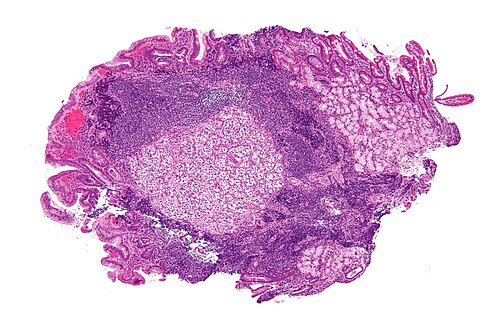

Clinical history

35 year old man, duodenal mass.

Intermediate magnification. H&E stain.